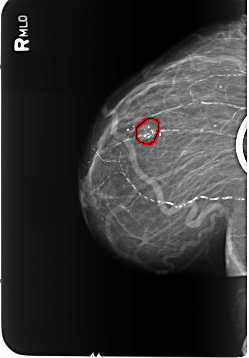

B_3481_1.RIGHT_MLO

FILE: B_3481_1.RIGHT_MLO.OVERLAY

TOTAL_ABNORMALITIES 1

ABNORMALITY 1

LESION_TYPE CALCIFICATION TYPE COARSE-PLEOMORPHIC DISTRIBUTION CLUSTERED

ASSESSMENT 2

SUBTLETY 5

PATHOLOGY BENIGN

TOTAL_OUTLINES 1

BOUNDARY